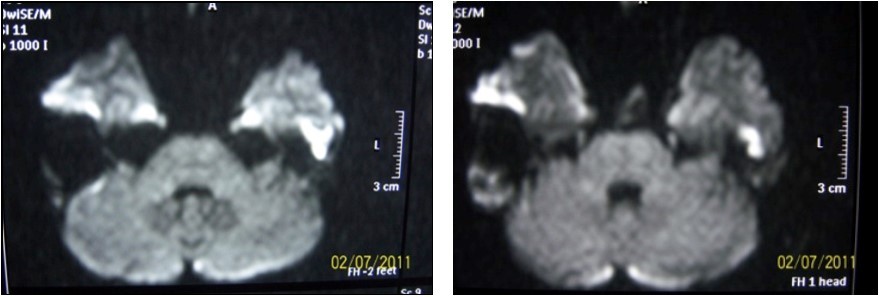

High intensity signals on diffusion MRI were considered to be supportive for cholesteatoma (Figure 3). 24 of patients (72.7%) were detected as cholesteatoma positive while 9 of them (27.3%) were negative on diffusion MRI (Table 1).

Figure 3.Diffusion MRI image of cholesteatoma

20 of 24 (83.3%) patients who had signs of cholesteatoma on preoperative diffusion MRI were positive intraoperatively while the remaining 4 (16.7%) were negative. 5 of 9 (55.4%) patients who had no evidence of cholesteatoma on MRI were positive intraoperatively while 4 (44.4%) were not (Table 1). There was no significant result obtained in terms of impact of diffusion MRI on detecting intraoperative cholesteatoma (p=0.09). In terms of indicatory strength of positive physical examination findings over presence of intraoperative cholesteatoma, sensitivity was found to be 96% whereas specifity was 87.5%, positive predictive value was 96% and negative predictive value was 87.5%. The area below the curve on ROC curve analysis was calculated as 98% (Table 3) (Figure 4).